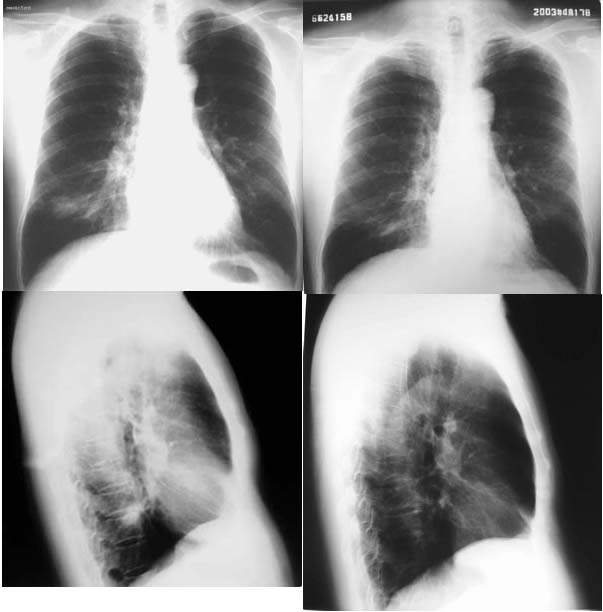

再来个空洞性肺癌,男,58岁,有咳嗽,咳痰,咯血,我看到片子时已经是治疗后复查了,第一次片子,空洞里充满了积液。